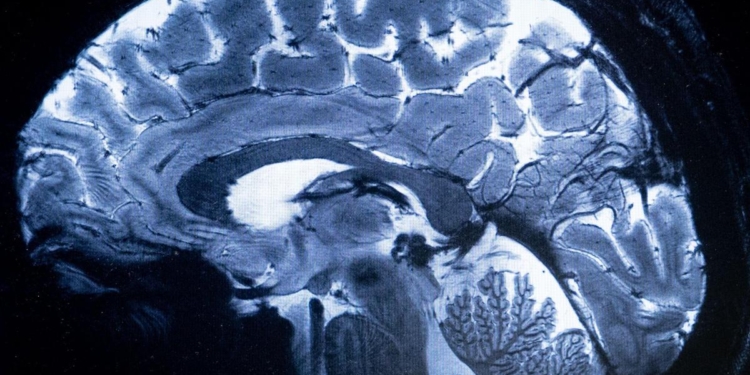

The study analysed the cerebral spinal fluid — a clear liquid surrounding and protecting the brain and spinal cord — of more than 100 schizophrenia patients and healthy people